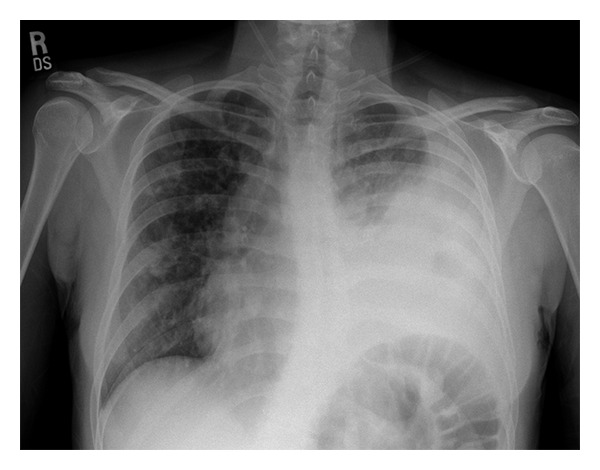

Visual input constitutes a vital component of the medical domain, supplying indispensable information in healthcare environments. Healthcare professionals extensively depend on visual cues for diagnosis, monitoring, and treatment of patients. Medical imaging technologies, such as X-rays, CT scans, and MRIs, offer unparalleled insight into internal organs, detecting diseases and abnormalities that may be invisible to the naked eye. Additionally, scientific figures and medical records, including plots, charts, and tables, are prevalent in the medical field. We propose linking visual experts with Med-Alpaca, as foundation model chaining presents a modular and highly adaptable framework for incorporating a diverse array of visual modules. Within this framework, any multimodal task can be divided into two essential stages: (1) the conversion of images to text, and (2) cognitive reasoning based on the derived text. In our context, visual experts (i.e., visual foundation models) transform medical images into an intermediate text representation. This converted data is then used to prompt a pretrained LLM, leveraging the inherent few-shot reasoning capabilities of LLMs to generate appropriate responses. Currently, our platform supports two distinct visual experts: Med-GIT and DePlot, chosen due to the widespread presence of radiology images and plots within the medical domain. The system's architecture is also designed to enable seamless integration of alternative medical visual experts, and we plan to incorporate additional medical visual foundation models as visual experts in the near future. The Med-GIT model represents a GIT: Generative Image-to-text Transformer for Vision and Language, fine-tuned specifically on the ROCO dataset to facilitate specialized radiology image captioning. The training procedure for the model is outlined in comprehensive detail in our publicly accessible Github repository.

Input 2: What is seen in the X-ray and what should be done? ![]()